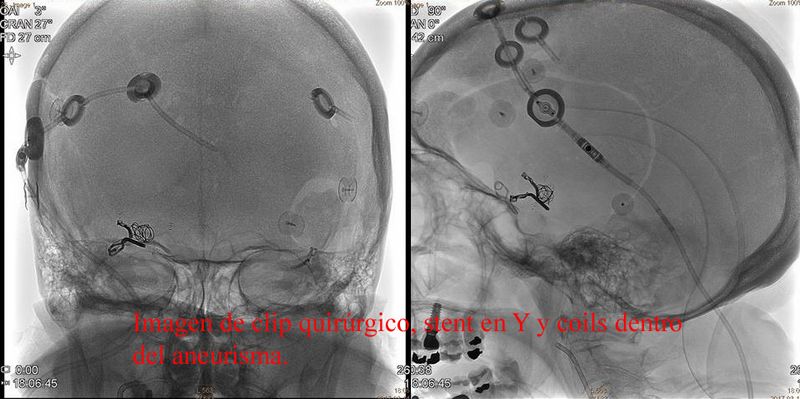

Aneurisma trat quirurgicamente